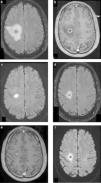

Abscesos cerebrales bacterianos inespecíficos. Pacientes con AC (a y d) bacteriano cerebeloso, (b y e) encefálico subcortical y (e y f) múltiples de distribución bilateral superficial y profunda. Se ilustra el comportamiento característico de estas lesiones con el realce anular clásico en (a, b y c) las secuencias ponderadas en T1 con contraste y (d, e y f) el intenso fenómeno de restricción en el centro necrótico en la difusión, típico de estas lesiones.

En las etapas precoces del proceso infeccioso bacteriano, cerebritis y fase de encapsulación primaria, la restricción no es tan marcada, por lo que existen dificultades al momento de realizar el diagnóstico diferencial15,18.

En la práctica, la distinción entre los tipos de AC únicamente con secuencias convencionales es muy compleja. Si utilizamos la DWI, sumado a un análisis minucioso de la morfología de las lesiones, el contexto clínico y el estado de inmunidad del paciente, se puede arribar al diagnóstico de forma más precisa.